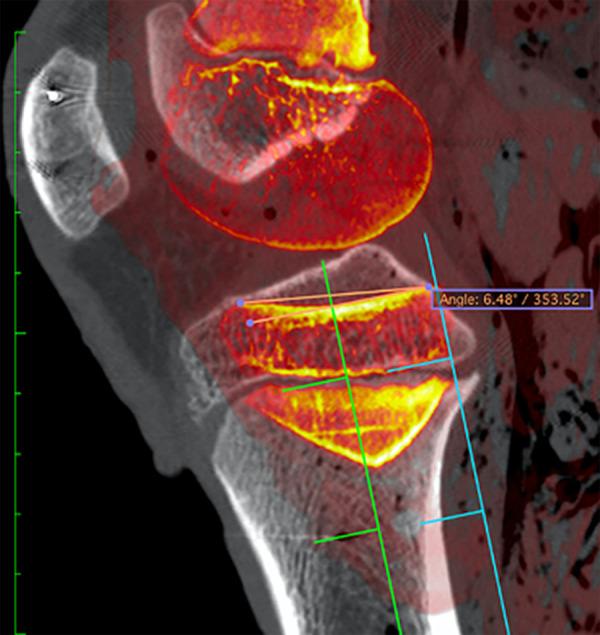

A total of 39 pediatric knee specimens with computed tomography scans were analyzed. Specimens analyzed were between the ages of 2 and 12 years. The PTS of each specimen was measured on sagittal computed tomography slices at 2 locations for the medial and lateral angles. The measurements were plotted graphically by age to account for the variability in development within age groups. The anterior medial and lateral tibial plateau widths were measured. The distance between the top of the tibial plateau and the physis was measured. The independent-samples test and analysis of variance were used to analyze the measurements.

The mean PTS angle for the medial and lateral tibial plateaus was 5.53° ± 4.17° and 5.95° ± 3.96°, respectively. The difference between the PTS angles of the medial and lateral tibial plateaus was not statistically significant ( > .05). When plotted graphically by age, no trend between age and PTS was identified.